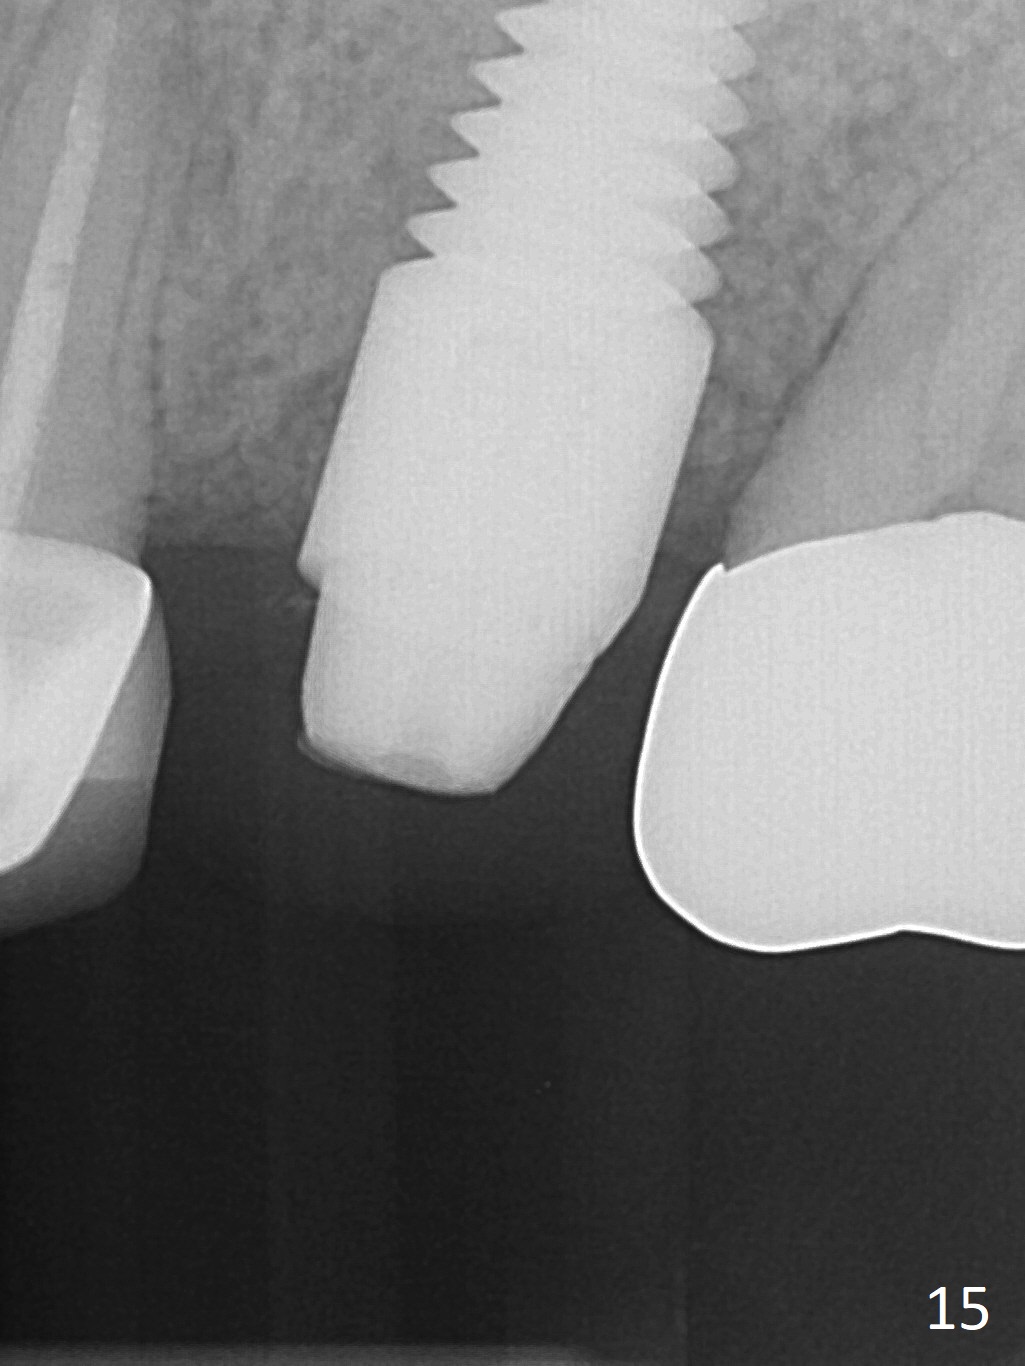

The patient is doing well 9 days postop. The immediate provisional is loose and over-sized. It is removed for trimming and reline; the socket and bone graft (Fig.8 *) are healing. It appears that an angled abutment is required next time of provisional revision. When an angled abutment is being placed 23 days postop (Fig.9), it appears to wiggle the implant due to its long leverage. Instead a healing abutment is placed. The implant is unstable 4.5 months postop with seemingly excessive bone-implant gap (Fig.10 <). The 5.5x9 mm implant is removed. A 5x17 mm tap is used to change the trajectory and sinus lift, followed by 6x17 one (Fig.11). Finally a 6x14 mm tissue-level implant is placed with insertion torque > 50 Ncm (Fig.12; vs. <20 Ncm (Fig.7,10)) and improved trajectory. An immediate provisional is fabricated to prevent the mesial drifting of the tooth #15 (Fig.13 P (*: occlusal clearance)). By using the taps and placing the longer implant, the sinus lift is more obvious (compare Fig.10 and 12 (*)). Sinus lift remains evident 3.5 months postop (Fig.14) with apparently osteointegration (Fig.15).